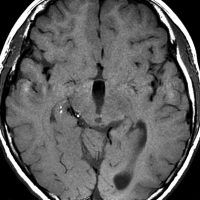

teratomaのparadoxical response

neurohypophyseal mixed germ cell tumorの若年成人男子例です。発症時のMRIでは大部分が増強されますが,腫瘍の右前方に脂肪組織を示す小さな信号域を認めます(上段左の単純MRI,上段右の増強MRI)。経蝶形骨洞生検術でmature teratomaとgerminomaの所見が得られました。ICE化学療法により増強される部分の腫瘍は消失しましたが,逆に下段左の単純MRIと下段中央のCTで認められる脂肪組織を含む部分が顕著に増大しました。この腫瘍は後に亜全摘出しました(下段右)が,病理所見は類皮腫でした。teratomaにおいてはこのような奇異な治療反応性 paradoxical response がみられることがあります。